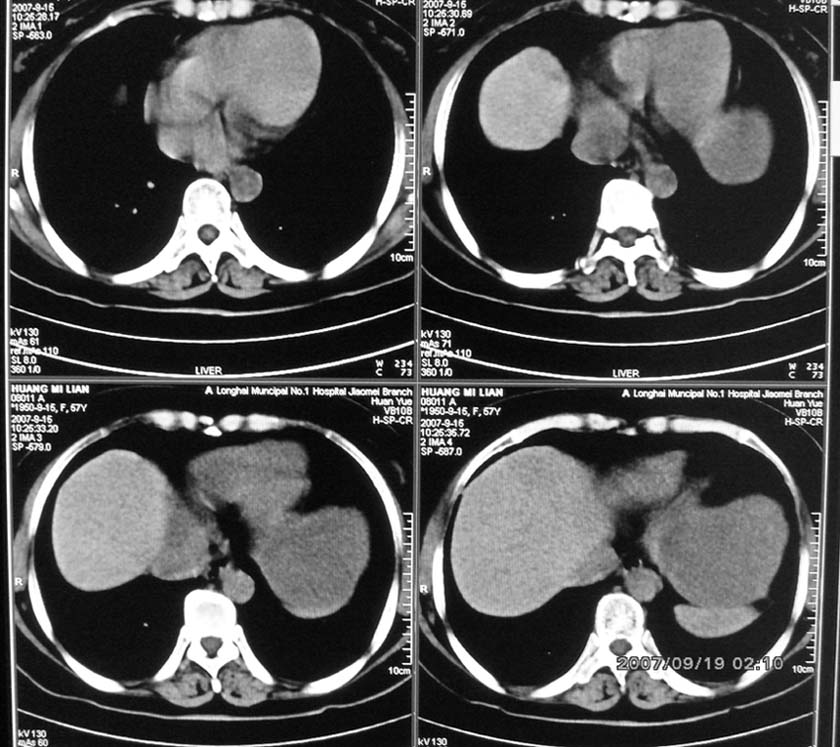

以下是引用逸风在2007-9-19 20:11:00的发言:[br]定位在肝左叶应该没有问题![br]ct显示肝左叶巨大低密度病灶,ct值30hu,密度欠均匀,里面似可见更低密度区;肝门及腹膜后未见明确肿大淋巴结.其与胃之间脂肪间隙存在;彩超提示病灶多发.[br]我个人觉得首先应该增强扫描,从平扫所见结合超声,首先应该考虑血管瘤.

以下是引用davisxuyong在2007-9-19 16:29:00的发言:[br]肝左叶大片状低密度灶,肝癌待排,建议增强。